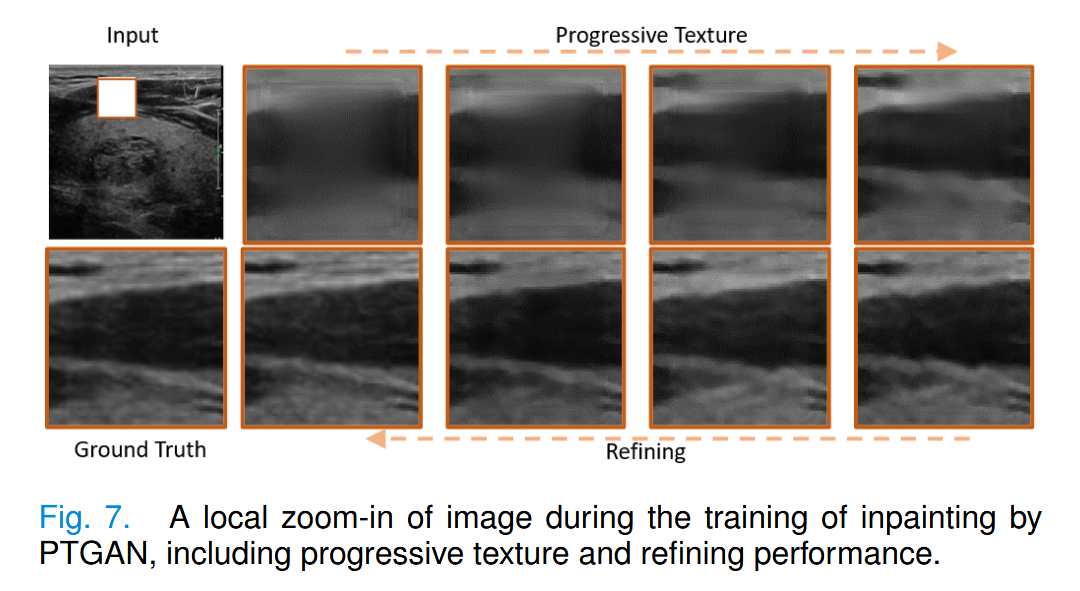

图7展示了我们方法中带有掩膜皮肤纹理图像的重建过程。

第一行从左到右展示了结构和纹理的逐步重建。第二行从右到左展示了细化模块对超声图像细节优化的效果。